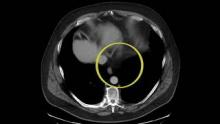

The authors present a case of a transgastric laparoscopic-assisted endoscopic resection in a 64-year-old man with an incidentally found 5.4 cm gastric GIST. The mass was located endoscopically near the gastroesophageal junction. Three transgastric ports were placed and the stomach was insufflated. The mass was excised with ultrasonic shears and removed endoscopically to avoid enlarging the gastrotomy. The mucosotomy was closed with running barbed suture. Final pathology demonstrated negative margins and he was discharged on postoperative day two. This technique offers a minimally invasive approach for removal of a mass near the gastroesophageal junction that may otherwise require a gastrectomy or esophageal resection.